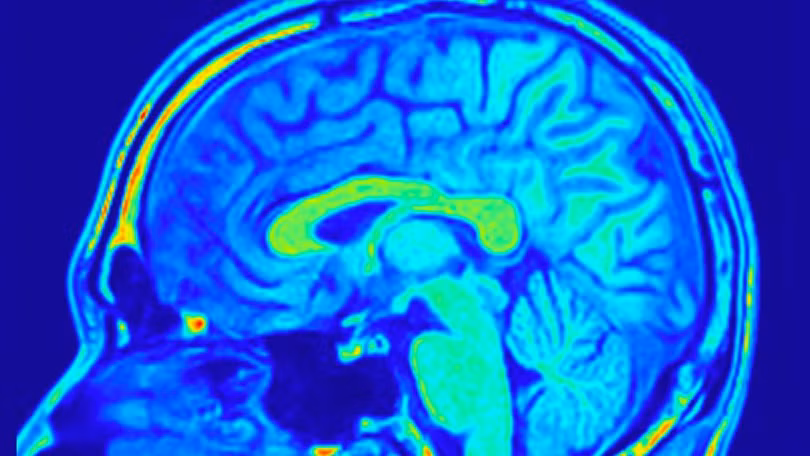

Hình chụp công hưởng từ não. Ảnh: FocalFinder/Shutterstock

Một bước đột phá quan trọng trong chẩn đoán ung thư vừa được công bố: AI có thể phát hiện các khối u não nhỏ đến mức thường bị bỏ qua bởi chụp cộng hưởng từ (MRI).